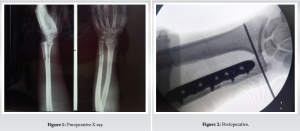

A 20-year-old male, presented to our emergency department with complaints of pain and loss of movement in his left wrist, following a fall on outstretched hand. There was no history of diabetes, hypertension, alcohol, and smoking. On examination, diffuse tenderness and swelling were present over the left wrist. No distal neurovascular deficit was noted. No other injuries were noted during the examination. Immobilization and analgesics were given in an emergency. Plain radiographs revealed distal 1/3rd shaft of ulna fracture with distal radioulnar joint dislocation (Fig. 1).

Radiographs of the elbow were also done which was normal The patient was prepared for operative intervention and necessary investigations were done. The subcutaneous approach was used and open reduction internal fixation was done using standard low-contact dynamic compression plate (Fig. 2). Distal radioulnar joint was reduced with the help of a pointed reduction clamp and a 2 mm k wire was inserted from ulna to radius. The challenge faced during this case was the reduction of radioulnar joint after ulna fixation. Radial deviation with traction and countertraction was done to reduce the DRUJ. We initially tried to reduce DRUJ first and fix the ulna afterward with holding the DRUJ using a reduction clamp but was not possible. So we fixed ulna first and reduced DRUJ later on. Postoperatively, the wrist was immobilized for 4 weeks. The K-wire was removed after 4 weeks. The gradual physiotherapy with wrist range of motion and grip strengthening exercises were started. Wrist range of motion was fully achieved in about 8 weeks and grip strength was also within preoperative status by 10 weeks. After that, all normal activities were allowed to patient which was done preoperatively by the patient. He was followed up at 2 weeks, 4 weeks, and then monthly thereafter. After 1 year of follow-up, the fracture has healed completely (Fig. 3) and had a satisfactory range of motion (Table 1). He was able to carry out his activities of daily living comfortably and his Disability of the Arm, Shoulder, and Humerus of the (DASH) [5] score was calculated to be 19.2.